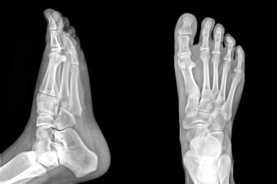

The Foot Institute is an association of Lloydminster Doctors specializing in the medical treatment of the foot and ankle, and is one of the largest groups of foot specialists in Alberta.

The Lloydminster Foot Institute is dedicated to the medical and surgical treatment of the foot. Our mandate is to provide the best possible medical, surgical and preventative treatment available for our patients. We do this by providing well-trained Doctors who are committed to treat and prevent all types of foot pain, biomechanical disorders, as well as all other problems relating to the feet.

At the Lloydminster Foot Institute, our Doctors are trained to specifically treat problems associated with your feet or ankles. Below are several of the most common problems that we see on a day to day basis: